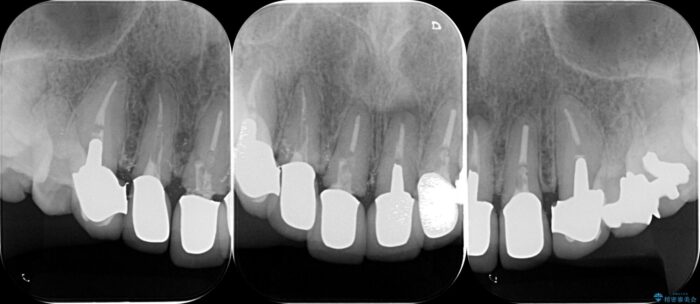

治療計画

装着されていたセラミックを除去したところ、歯ぐきの奥深くまで歯牙は削られ、歯ぐきの炎症・出血が著しくみられる状態でした。

この状態で再度セラミッククラウンの作製・装着を行ってもまた同じ状態となってしまうため、歯周外科を行い歯ぐきの状態を整備したのちセラミッククラウン治療をおこなっていきます。